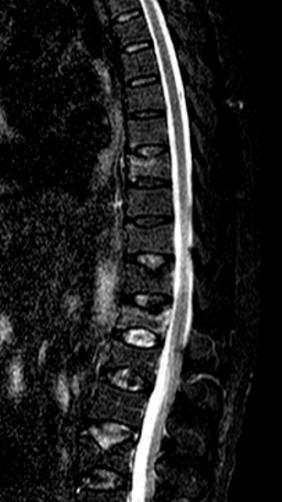

术前核磁共振检查明确T8.12椎体骨折,为疼痛责任椎体;经皮穿刺微创椎体成形术后复查可见椎体高度恢复良好,骨水泥弥散满意。

术前过伸位X、CT检查,早期诊断